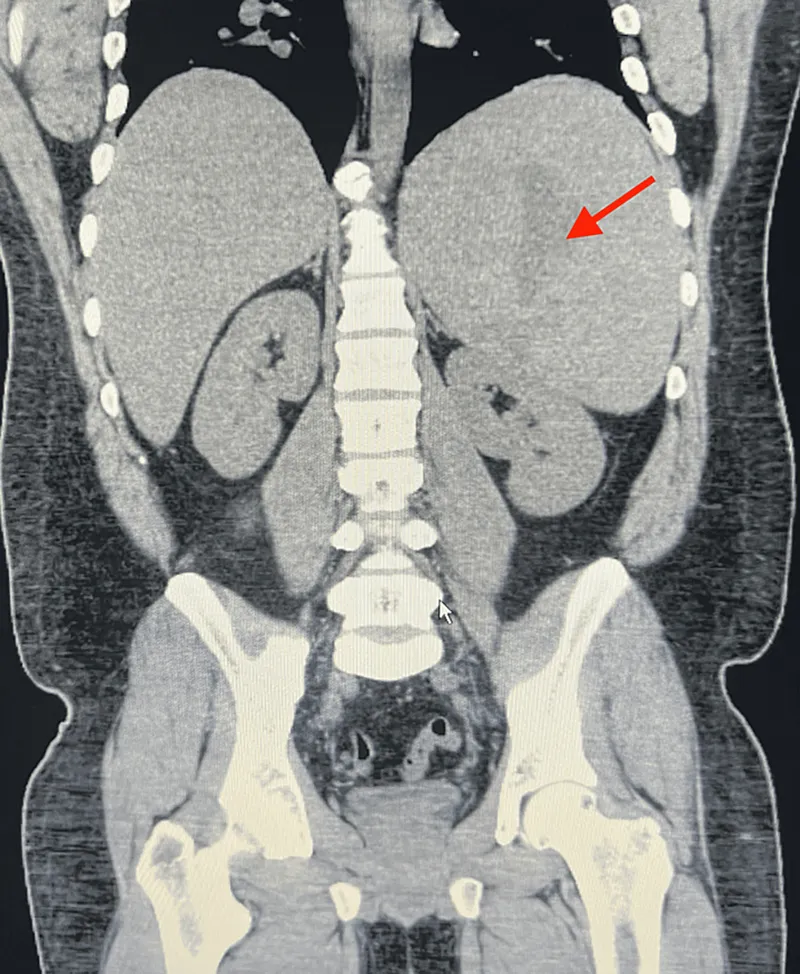

Splenomegaly & Diffuse Disease - The Swollen Spleen

- Definition: Spleen length > 12-13 cm or weight > 200g.

- Common Causes:

- Congestive: Portal hypertension (cirrhosis), heart failure.

- Infective: Malaria, Kala-azar, EBV, TB.

- Hematological: Leukemias, lymphomas, hemolytic anemias, myeloproliferative disorders.

- Storage: Gaucher's, Niemann-Pick.

- Inflammatory: Sarcoidosis, SLE.

- Splenomegaly (>12 cm length): common, due to portal hypertension, hematological disorders.